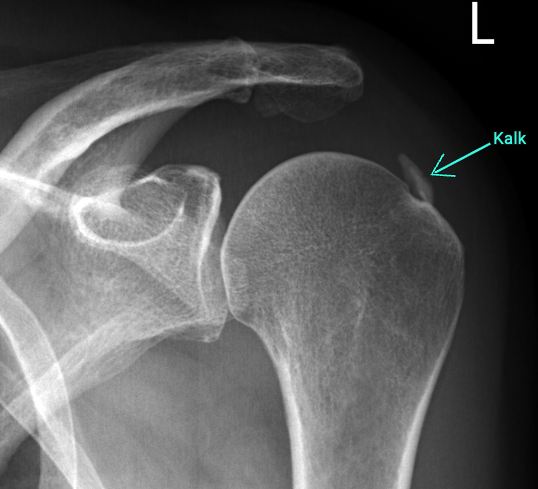

Typisch sind stechende Schmerzen, die vor allem nachts oder bei bestimmten Bewegungen auftreten, etwa beim Anheben des Arms. In akuten Phasen können die Beschwerden so stark sein, dass alltägliche Tätigkeiten kaum noch möglich sind. Die Diagnose der Kalkschulter lässt sich einfach mit einem Röntgenbild stellen.

Die Behandlung richtet sich nach der Ausprägung und den Beschwerden. In vielen Fällen helfen konservative Maßnahmen wie Schmerzmedikation oder Kortison Injektionen in den Schleimbeutel unter dem Schulterdach